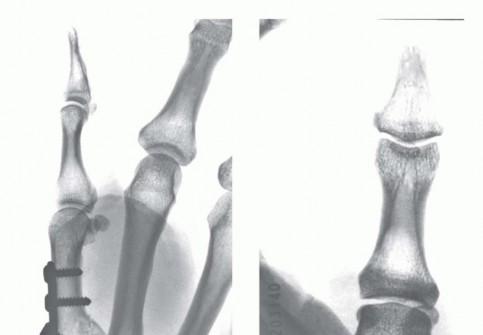

Open Reduction and Internal Fixation (ORIF) - Wagner Approach

For fractures with large volar-ulnar fragments (>20% of the articular surface), displaced Rolando fractures, or cases where closed reduction fails, ORIF is unequivocally mandated. The classic Wagner approach provides unparalleled exposure to the thumb CMC joint. A curvilinear incision is made along the glabrous border of the thenar eminence, curving dorsally at the level of the CMC joint.

Meticulous superficial dissection is required to identify and protect the sensory branches of the superficial radial nerve dorsally and the palmar cutaneous branch of the median nerve volarly. The thenar musculature (abductor pollicis brevis and opponens pollicis) is sharply elevated from the metacarpal shaft and retracted volarly. The joint capsule is then incised longitudinally or in an L-shaped fashion to expose the articular surface. The hematoma is evacuated, and the fracture fragments are meticulously debrided of interposed soft tissue.

For a large fragment Bennett fracture, the shaft is reduced to the volar-ulnar fragment using a pointed reduction clamp. Provisional fixation is achieved with a K-wire. A 1.5mm or 2.0mm lag screw is then placed perpendicular to the fracture plane. The near cortex must be overdrilled (gliding hole) and the far cortex underdrilled (thread hole) to achieve true interfragmentary compression. The screw head should be countersunk to prevent hardware prominence beneath the thenar muscles.